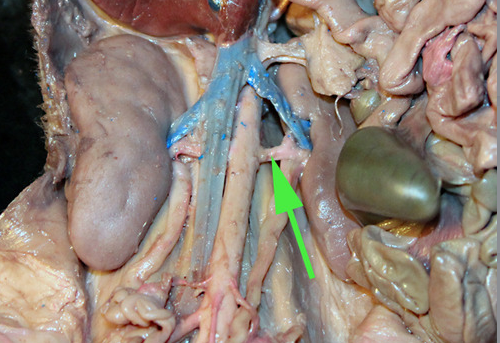

The vessel marked by the green arrow is the inferior vena cava

The vessel marked by the green arrow is the inferior vena cava

what is the green arrow pointing at? //abdominal aorta

The vessel marked by the green arrow is a renal

artery.